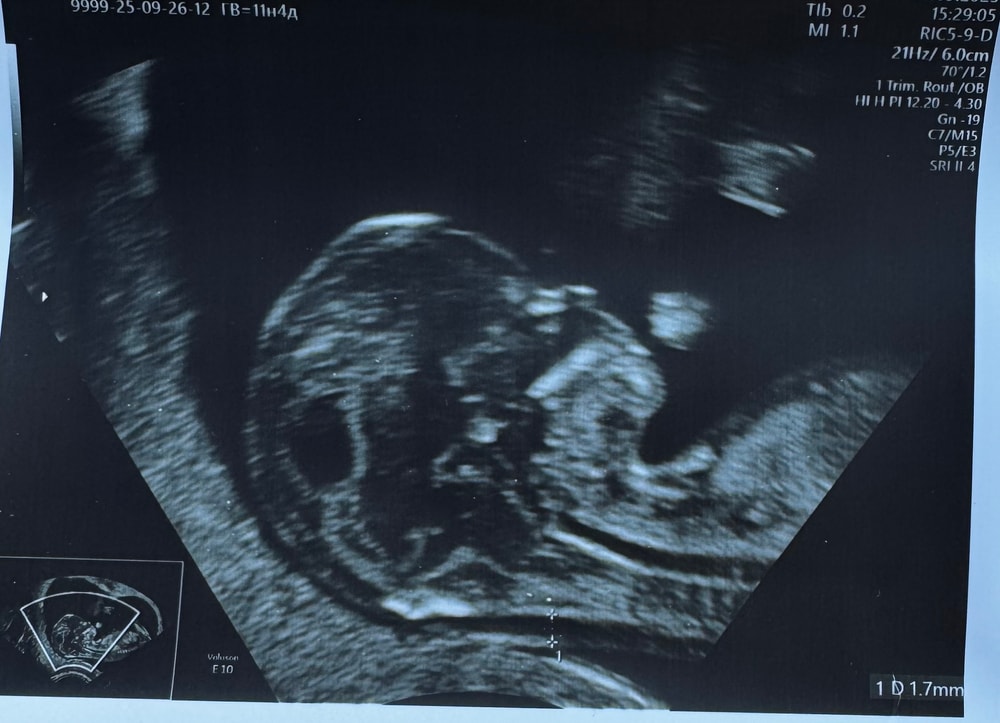

Svoya, а это уже 11+4)) Изображение